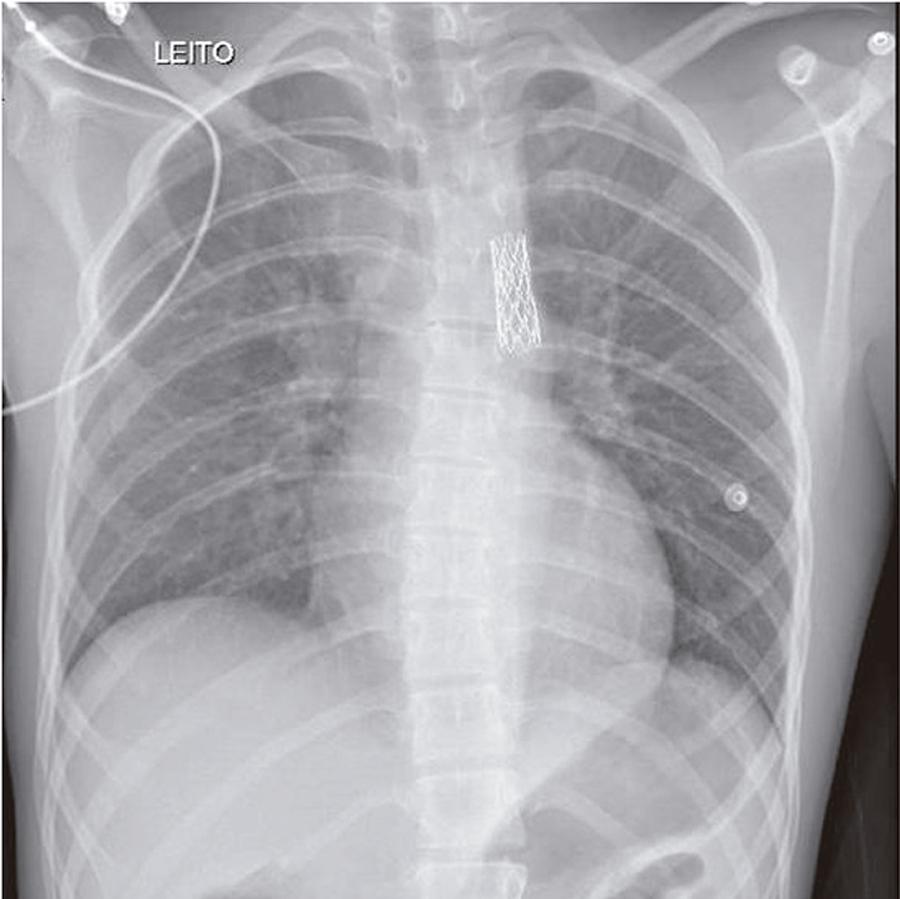

Case 1/2020 – Very Accentuated Isthmic Coarctation of the Aorta in a Young Individual with Arterial Hypertension Relieved by Interventional Catheterization

Arterial hypertension had been detected 6 months before, after study-related stress in a 16-year-old individual. At the time, diagnostic images (echocardiography and angiotomography) confirmed the presence of accentuated isthmic coarctation of the aorta, with many collaterals that filled the descending aorta. Blood pressure was 170/80 mmHg, which decreased to 130 to 150/80 mmHg with propranolol-80 mg/day. He had been previously submitted to surgery for atrial septal defect closure at 4 years of age. He reported fatigue at exertion since a few months before.

Physical examination: Good overall status, eupneic, acyanotic, wide pulses in the upper limbs and absent in the lower limbs. Weight: 45.5 Kg, Height: 163 cm, right upper limb BP and left upper limb BP = 155/80 mmHg, HR: 55 bpm. Aorta easily palpated at the suprasternal notch.